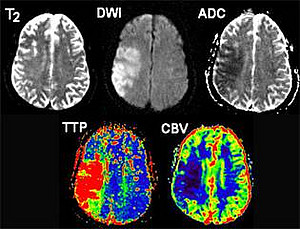

• Kontrastmittelgestützte Perfusionsbildgebung des Gehirns mittels MRT und CT.

• Ermittlung und Validierung neuer Parameter, welche aus den kontrastmitteldynamischen MRT-Untersuchungen gewonnen werden.

• Entwicklung und Evaluierung neuer Berechnungsmethoden für PWI Parameterbilder.

• Volumetrische Auswertungen von PWI-Parameterbildern: "DWI - PWI Mismatch-Konzept".